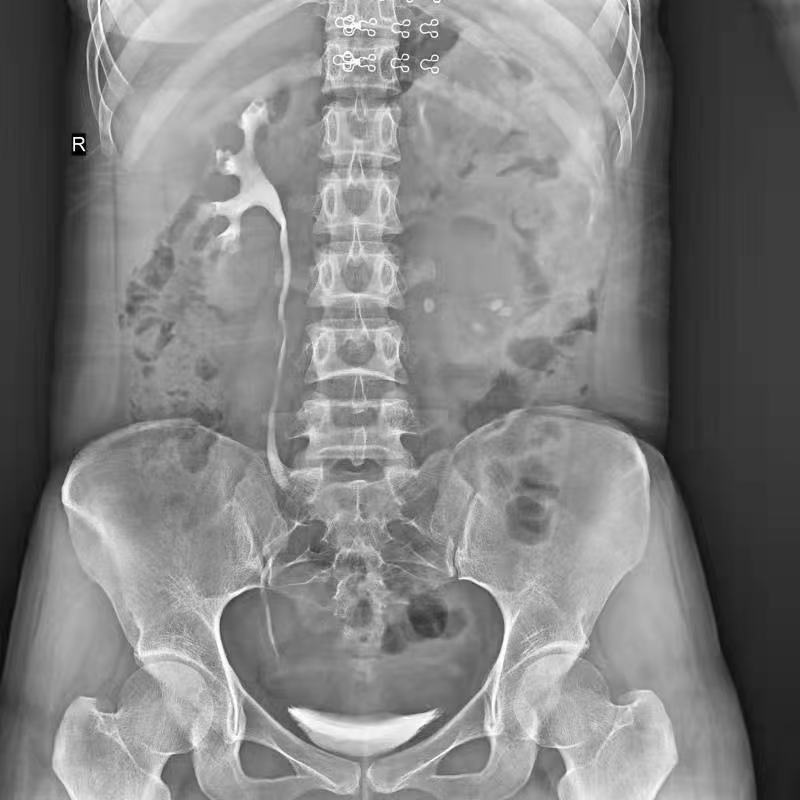

全自動(dòng)拼接

●呈現(xiàn)全下肢或全脊柱圖像

●在脊柱及下肢畸形矯正手術(shù)治療中,為術(shù)前方案制定和術(shù)后復(fù)查提供精準(zhǔn)測(cè)量

●有效解決傳統(tǒng)X光片不能一次成像問(wèn)題,為患者提供更加優(yōu)質(zhì)的醫(yī)療服務(wù)

Clinical picture

臨床圖片